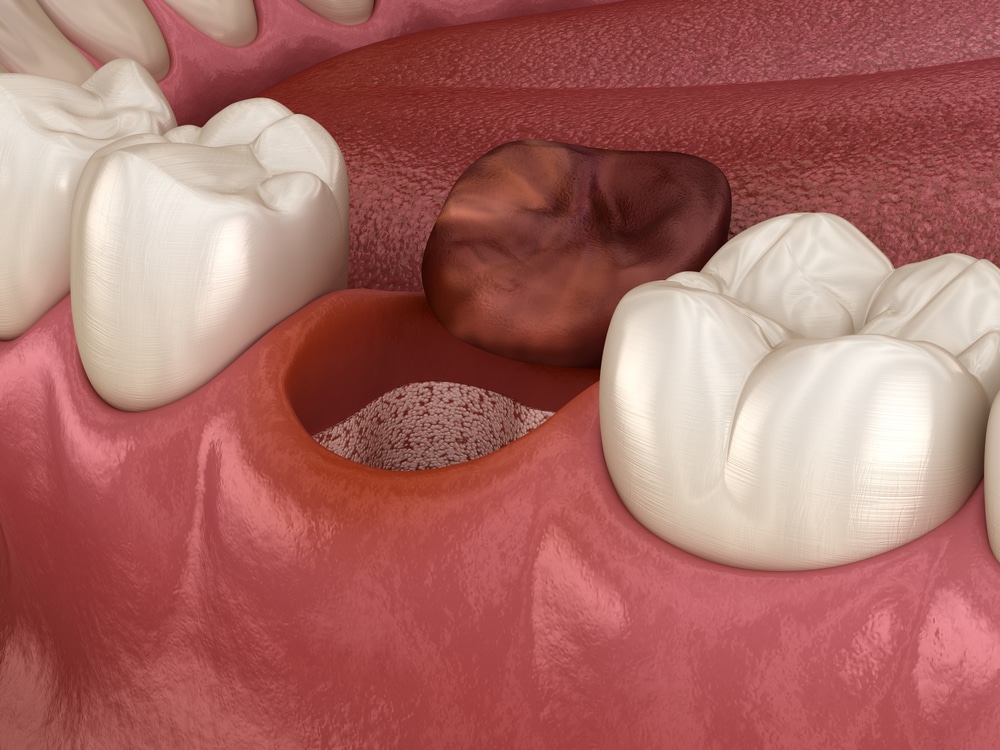

Diş çekimi sonrası iltihaplanma, tıbbi adıyla alveolit, çekim bölgesinde oluşması beklenen kan pıhtısının oluşmaması veya erken dönemde yerinden çıkması sonucu meydana gelir. Normal bir iyileşme sürecinde, çekilen dişin bulunduğu boşlukta bir kan pıhtısı oluşur. Bu pıhtı, yaranın iyileşmesini sağlayan doğal bir “koruyucu örtü” gibidir. Ancak bu pıhtı kaybolursa, kemik dokusu ve sinir uçları açıkta kalır, bu da şiddetli ağrıya, kötü ağız kokusuna ve enfeksiyona yol açabilir.

Kuru soket, tıbbi adıyla fibrinolitik alveolit, alveolitin en yaygın formudur. Normal şartlarda diş çekimi sonrasında oluşan boşlukta bir kan pıhtısı oluşur ve bu pıhtı, iyileşme sürecinin sağlıklı ilerlemesi için kritik öneme sahiptir. Ancak bazı durumlarda bu kan pıhtısı ya hiç oluşmaz ya da erken dönemde yerinden oynar veya erir. Bunun sonucunda kemik dokusu ve sinir uçları açıkta kalır. Bu durum hem enfeksiyona zemin hazırlar hem de şiddetli, zonklayıcı bir ağrıya yol açar.

- Boş diş yuvasının açık ve kuru görünmesi (kan pıhtısının olmaması)